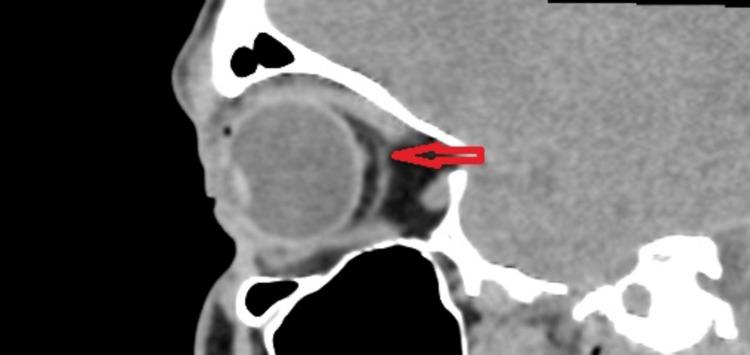

In this case report, we present the rare occurrence of supernumerary extraocular muscles (SEOM) in a 35-year-old male with hyperthyroidism. SEOMs are unusual anatomical variations involving extraocular muscles that deviate from the typical muscle arrangement in the eye. While SEOMs are rare, they can have diverse clinical manifestations, including restrictive strabismus and lid abnormalities. In this case, the patient displayed right-sided lid retraction and an asymmetrical palpebral aperture, which raised concerns about a potential association with thyroid eye disease. However, imaging revealed that the SEOM was anatomically connected to the superior rectus muscle, possibly contributing to the observed lid retraction. Understanding the complexities of SEOM and its potential interactions with conditions like thyroid ophthalmopathy is crucial for accurate diagnosis and management. Further research is needed to fully comprehend the development and clinical impact of SEOMs due to their rarity and limited knowledge in the medical literature.

在本病例报告中,我们呈现了一名35岁甲状腺功能亢进男性罕见的额外眼外肌(SEOM)情况。SEOM是涉及眼外肌的异常解剖变异,偏离了眼睛中典型的肌肉排列。虽然SEOM很罕见,但它们可具有多种临床表现,包括限制性斜视和眼睑异常。在本病例中,患者表现为右侧眼睑退缩和睑裂不对称,这引发了对其与甲状腺眼病潜在关联的担忧。然而,影像学显示SEOM在解剖学上与上直肌相连,这可能是观察到的眼睑退缩的原因。了解SEOM的复杂性及其与甲状腺眼病等病症的潜在相互作用对于准确诊断和管理至关重要。由于SEOM在医学文献中罕见且知识有限,需要进一步研究以全面理解其发育和临床影响。